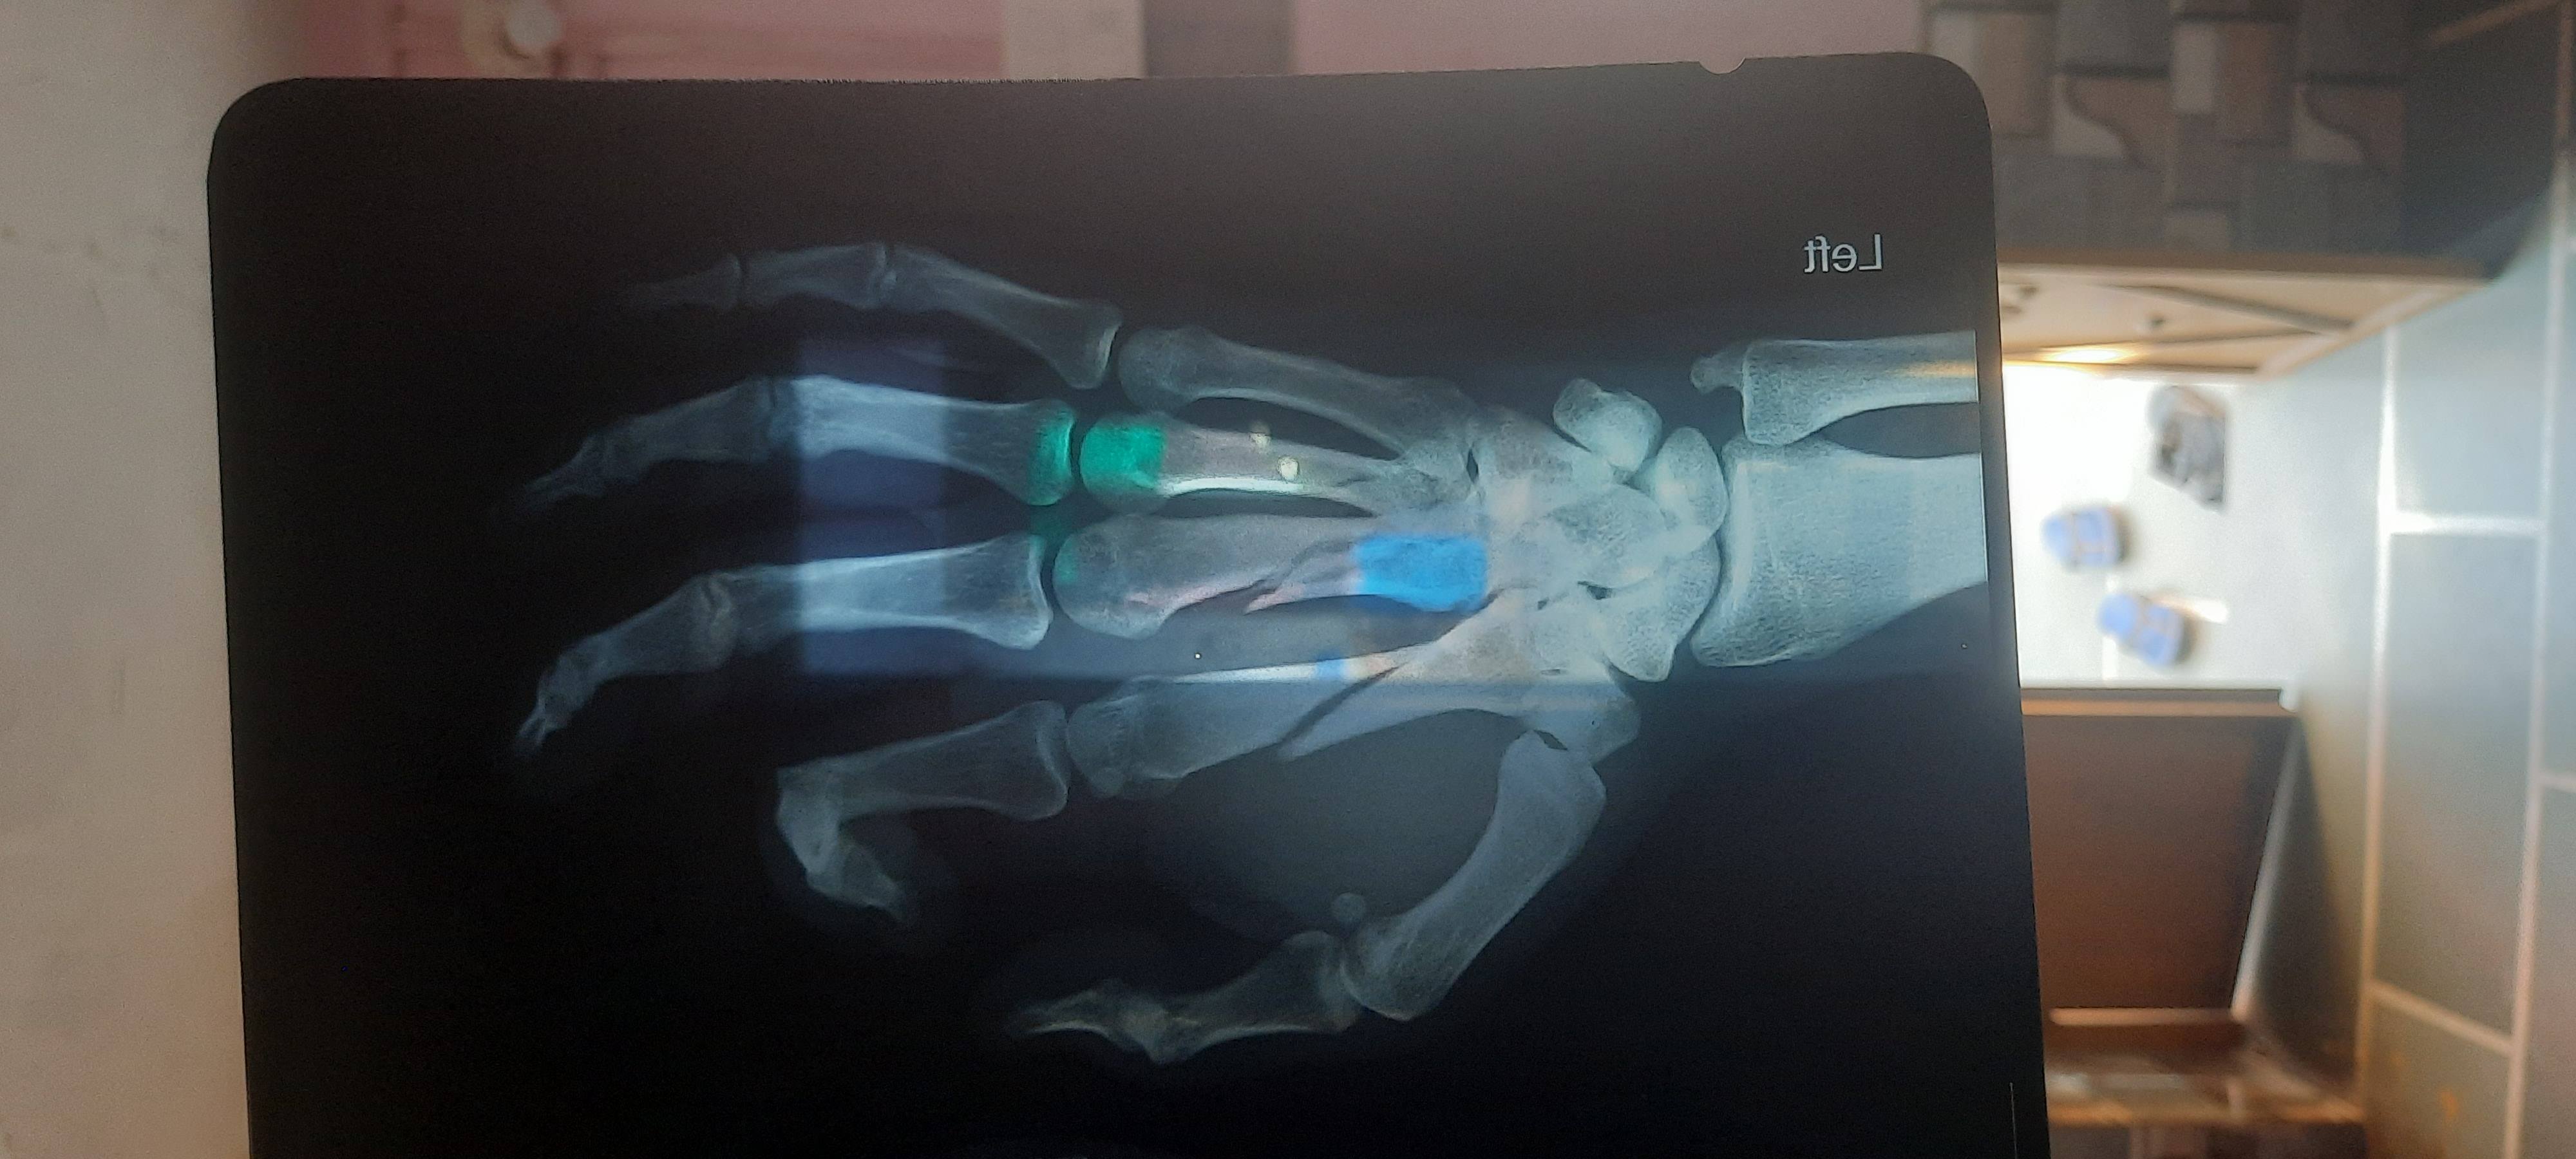

Dheeraj Kumar odichya